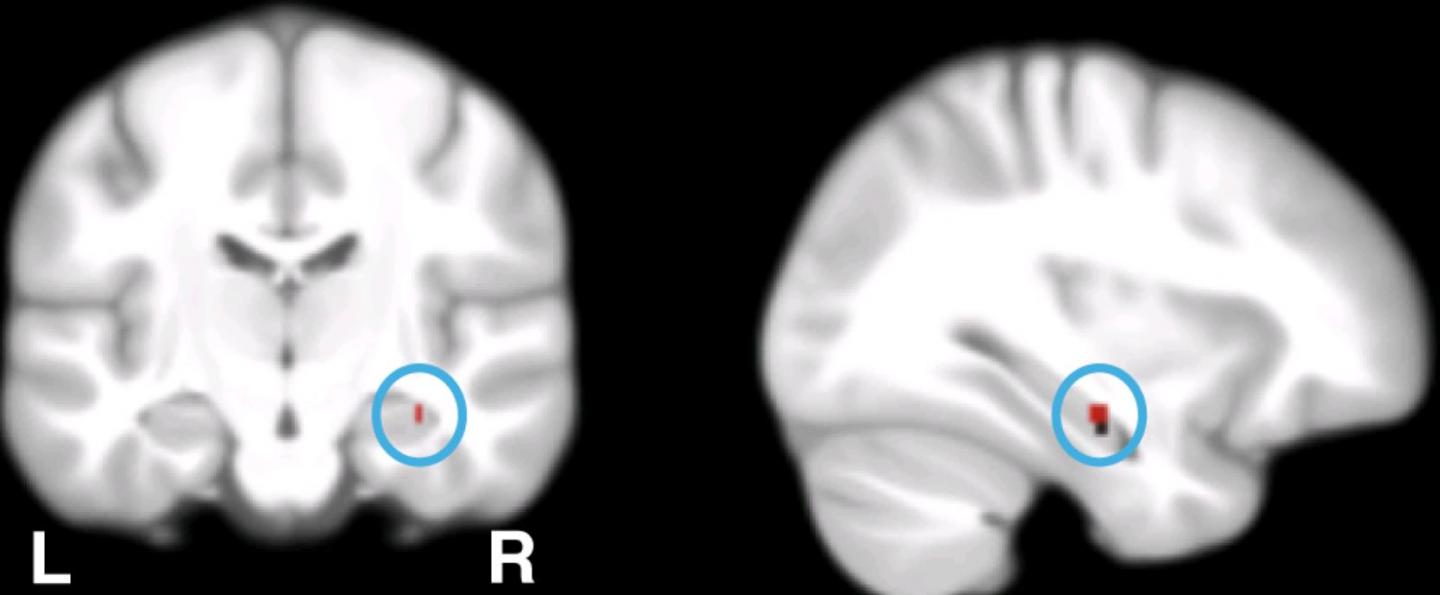

The study identified genes responsible for the concentration of calcium ions in the cell as central players of physiological and disease processes in the brain. Calcium genes stand in mutual relationship with memory performance of young and older healthy adults as well as with the function of the hippocampus, a brain region that is central to intact memory. Furthermore, calcium genes correlate with the risk for Alzheimer disease. The results contribute to the understanding of the complex processes that lead to memory disorders, such as Alzheimer's.